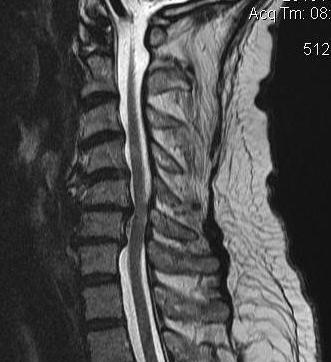

MRI

1. Space available for cord (SAC)

- Sagittal diameter of spinal canal - sagittal diameter spinal cord

- normal (17mm)

- relative (13mm)

- absolute stenosis (10mm)

Reduced by disc / osteophytes / OPLL / deformity / instability

Single level stenosis Double level stenosis Multi-level stenosis